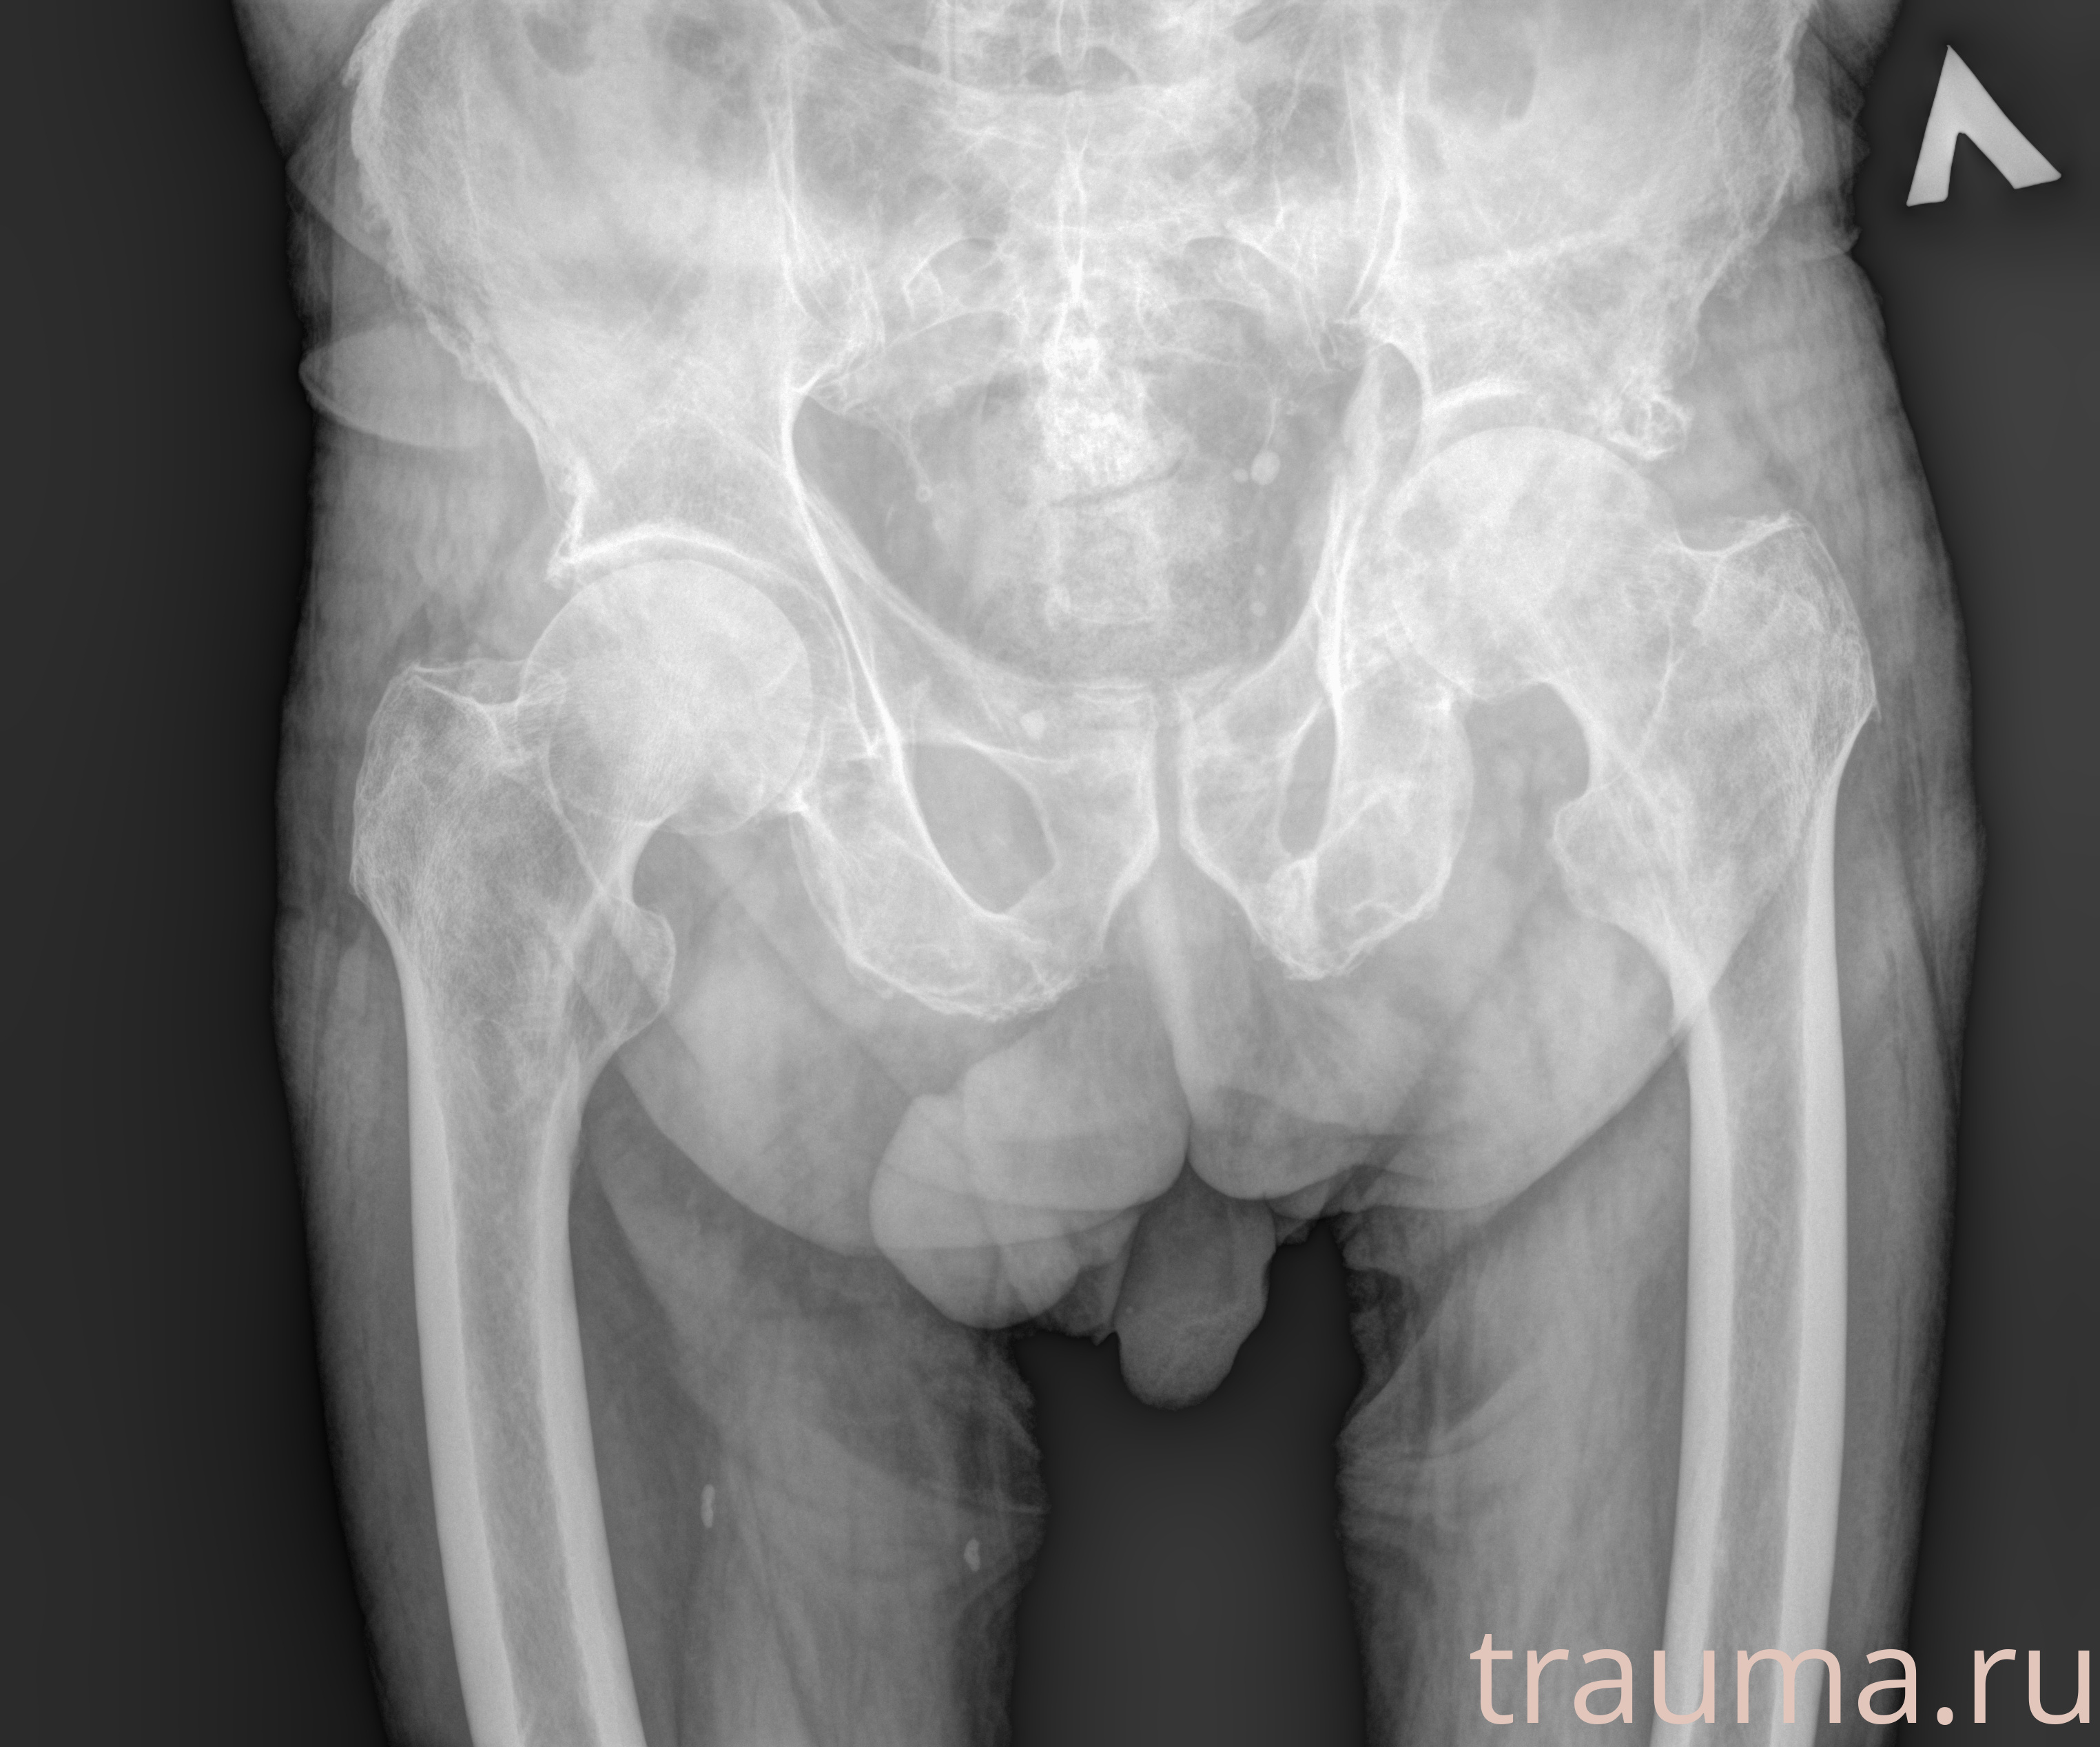

Рентген на дому: по вашему адресу приезжает врач-рентгенолог, травматолог-ортопед с мобильным рентгеновским аппаратом, проводит диагностику травмы или заболевания, делает необходимые рентгенограммы, дает рекомендации по дальнейшему лечению. Получить качественные снимки в домашних условиях возможно благодаря уникальной методике, разработанной МосРентген Центром для института  Склифосовского